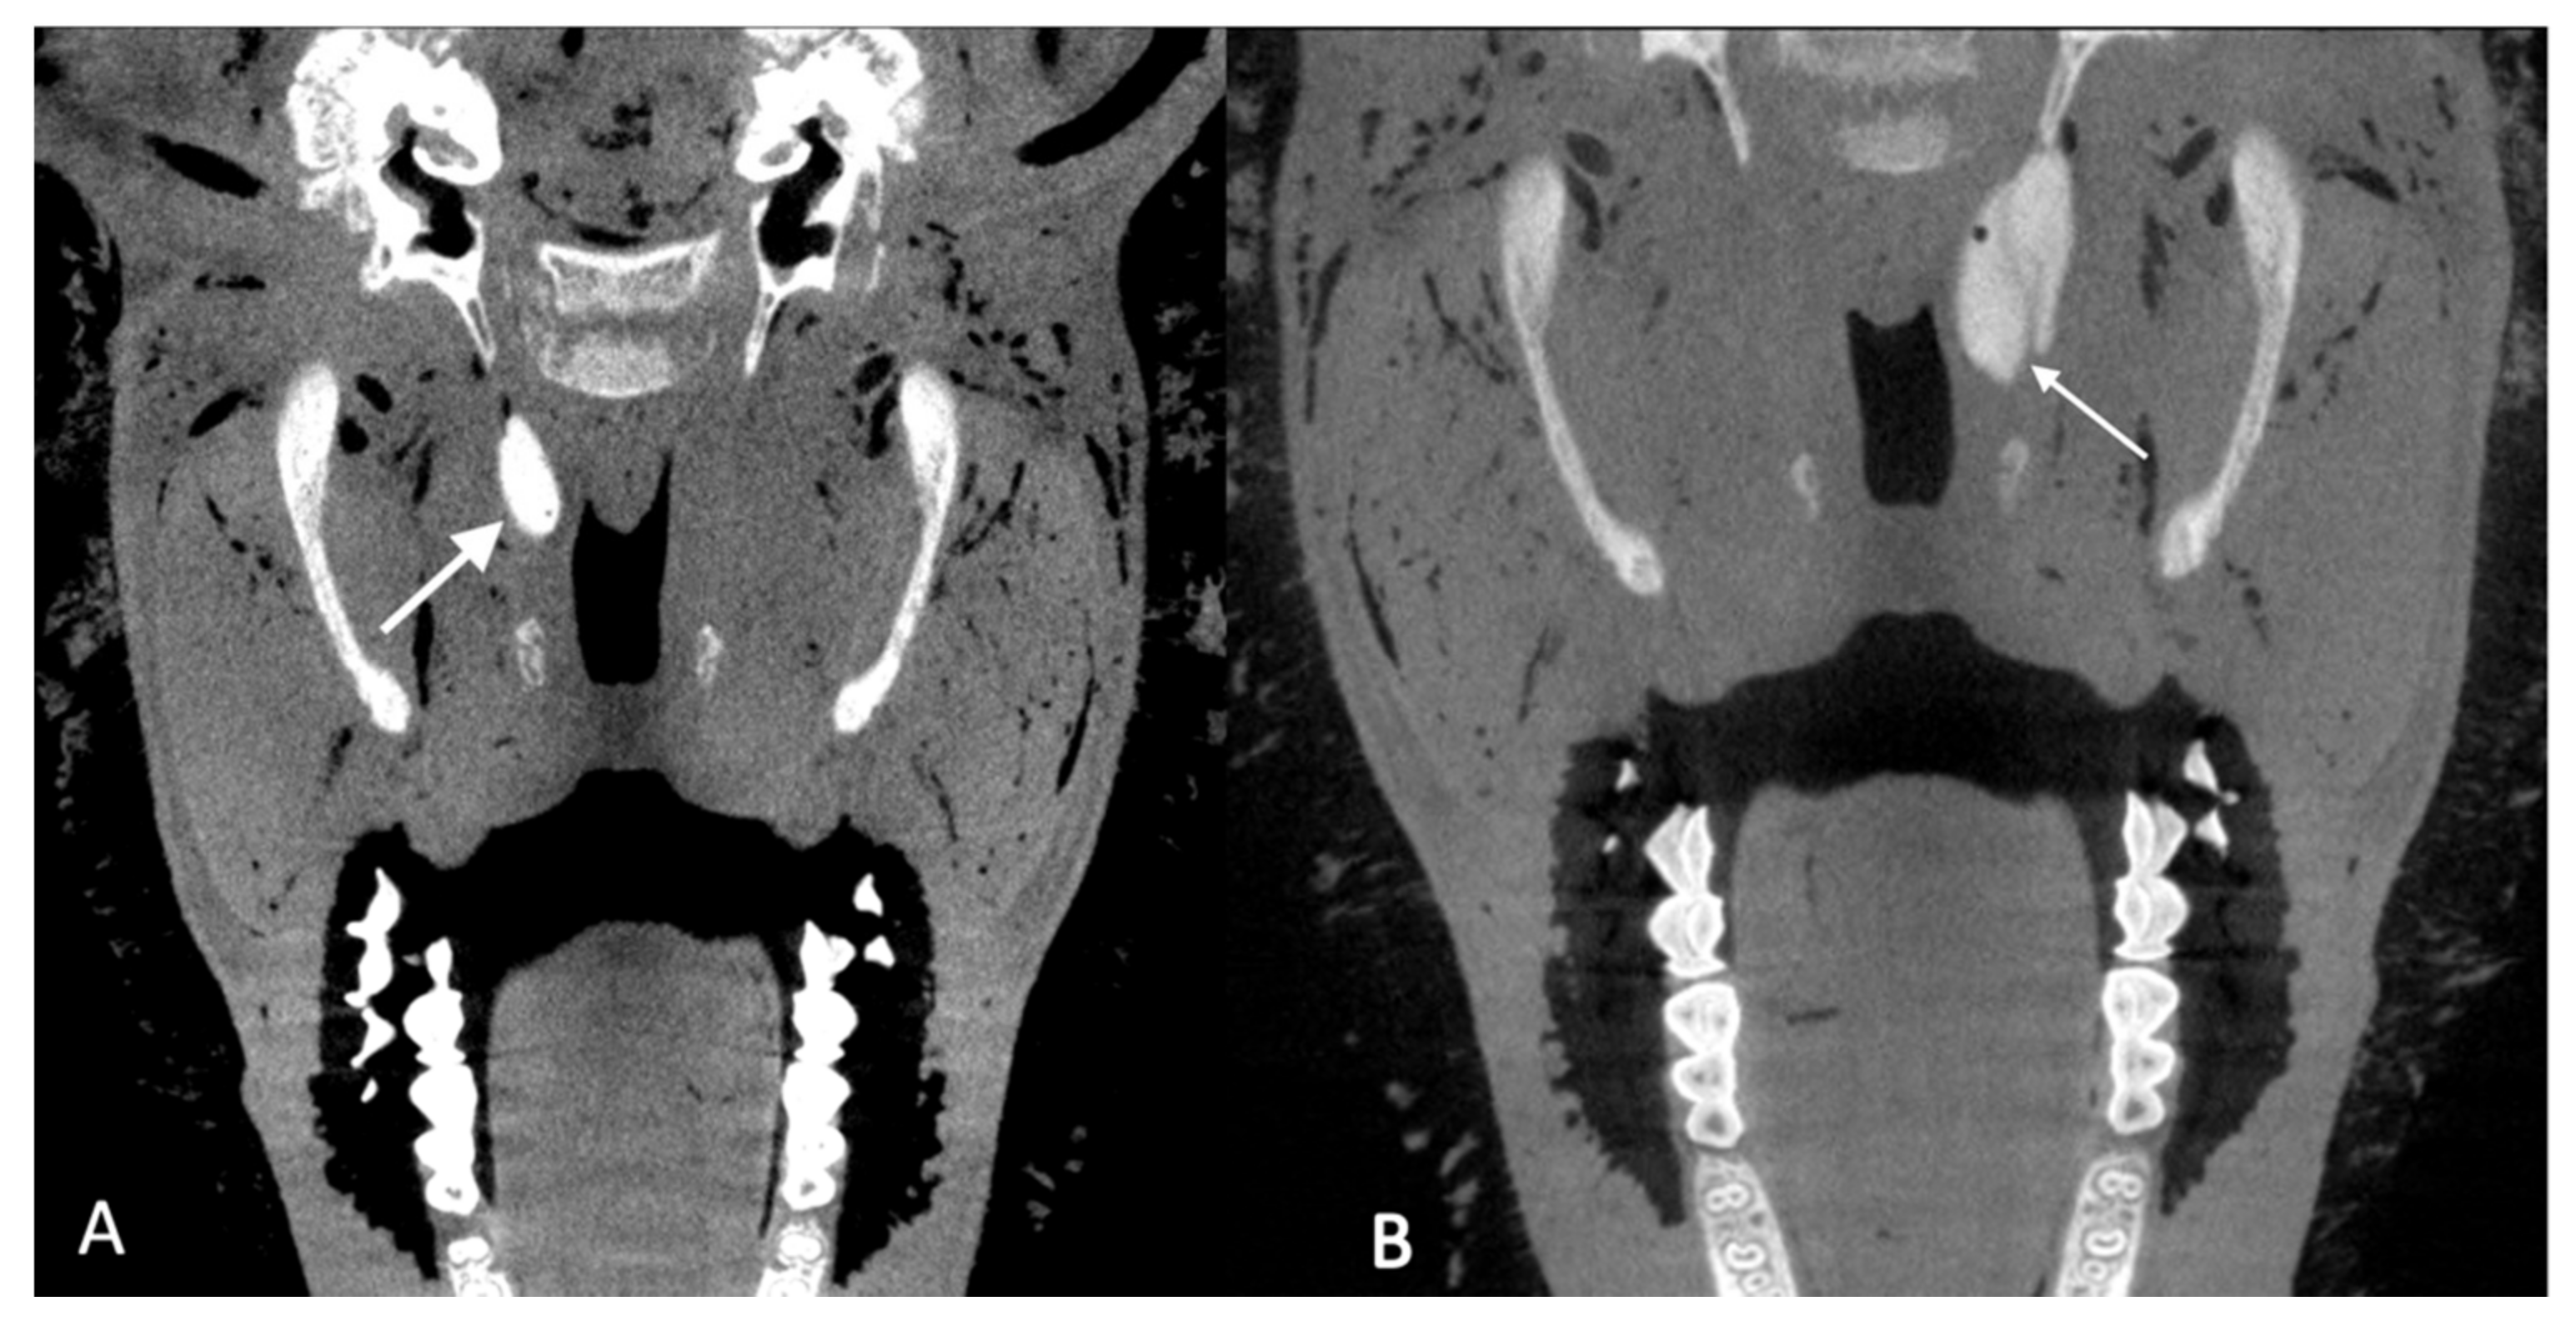

3.2.4. Imaging